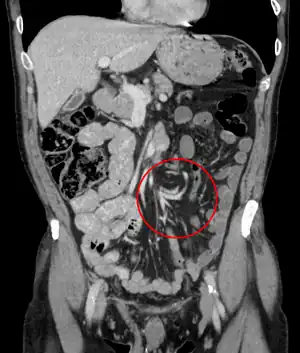

| Coronal CT of the abdomen, demonstrating a volvulus as indicated by twisting of the bowel stock | |

CT scan of a small bowel volvulus. It shows two juxtaposed segments of narrowing, which is the spot of mesentery rotation. The other signs indicate strangulation. -